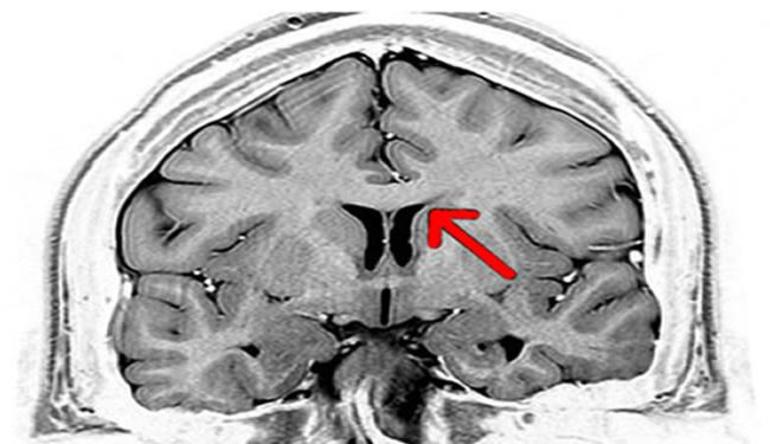

Гипоплазия — это специфический порок развития, при котором артерии имеют слишком маленькие размеры. Если кровообращение в других отделах мозга нормальное, патология может развиваться бессимптомно. Гипоплазию можно выявить только при комплексной диагностике работы головного мозга, и она хорошо видна на МРТ.

Аплазия — это состояние, при котором Виллизиев круг не замкнут из-за отсутствия соединяющей артерии. Это отклонение может развиваться как в передней, так и в задней части, однако последний вариант встречается гораздо чаще. Если артерия присутствует, но развита слабо, диагностируется частичная разомкнутость круга. Обследование разомкнутого круга проводится с помощью магнитно-резонансной томографии. Причиной данной патологии является остановка развития на этапе формирования плода.

Магнитно-резонансная томография (МРТ) на сегодняшний день считается самым точным методом обследования. Процедура проводится на магнитно-резонансном томографе, который воздействует магнитным полем на клетки организма и фиксирует их реакцию. Этот метод позволяет получить детальную информацию о состоянии различных органов, включая сосудистую систему. Поскольку обследование неинвазивное, оно считается безопасным и не предполагает использование радиоактивного облучения.